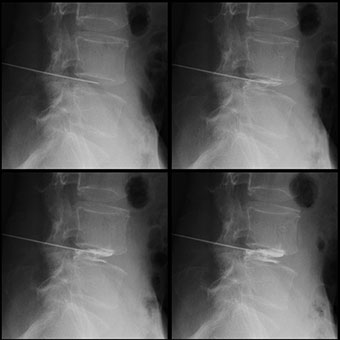

肝胆系検査

経皮的肝胆管造影法(PTC:Precutaneos Transhepatic Cholangiography)という、皮膚もしくは肝臓より肝内胆管に穿刺し、胆道を造影する検査です。また、経皮経肝胆管ドレナージ(PTCD:PTC-drainage)という、PTCチューブを留置し、胆汁を排泄する治療も行っています。